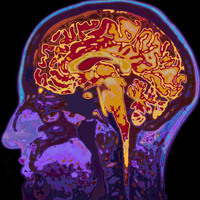

Growing concerns over severe neurological reactions to Covid-19 vaccines have intensified following reports of life-threatening brain inflammation linked to AstraZeneca’s jab. In France, a previously healthy 60-year-old man developed meningoencephalitis — a dangerous swelling of the brain and spina…